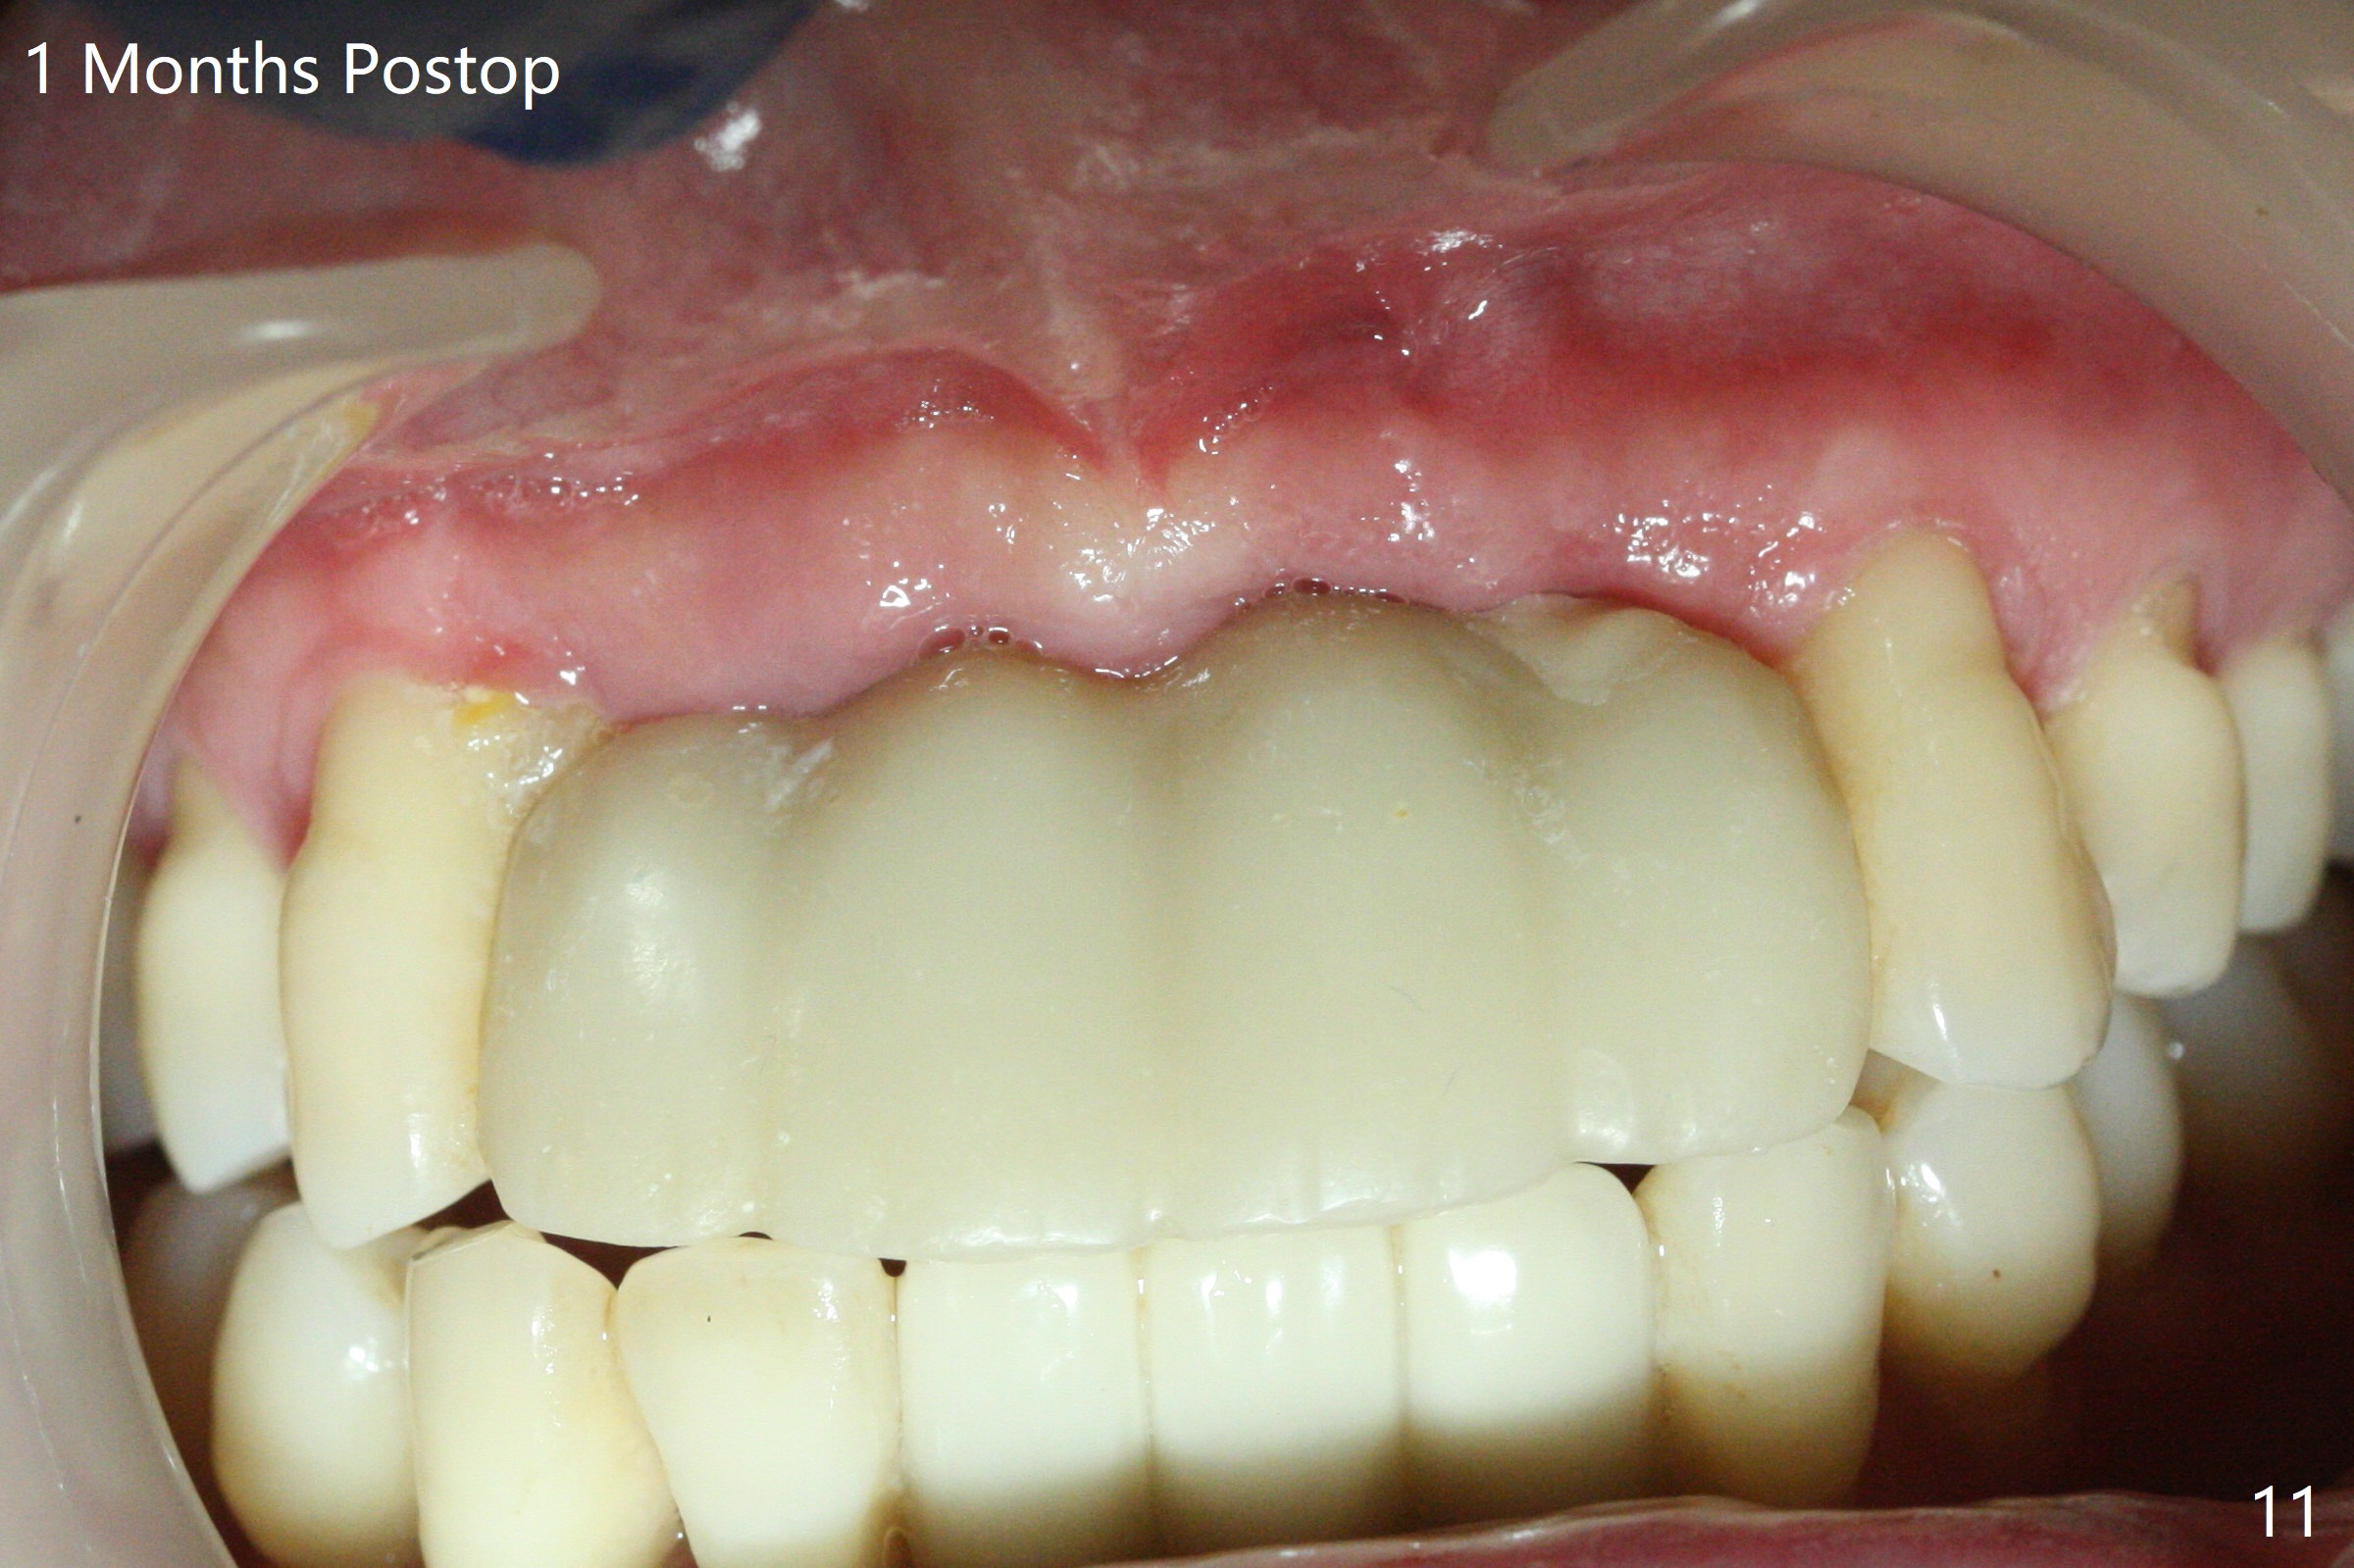

Although the ridge of the maxillary anterior ridge looks moderate in width (Fig.1), the bone is ~4 mm buccopalatally. Suction down surgical stent (Fig.2') made from the lab-fabricated provisional (Fig.2) will be used to check the position and trajectory of osteotomies. PAs taken after initial osteotomies (1.2 mm drill) show those at the central incisors tend to be mesial (close to the Incisive Canal *), while those at the lateral incisor sites distal (Fig.3,4). After adjustment, the position and trajectory of the osteotomies are acceptable (Fig.5,6). To reduce the chance of perforating the Incisive Canal (Fig.3,4 *), 2.5 mm 1-piece implants are inserted with >40 Ncm (Fig.7,8). After deep placement of the implants, Vanilla graft is placed at the crest (Fig.9,10 *). An immediate splinted provisional is fabricated from the suction down stent. The gingiva is healthy around the provisional (Fig.11) and the implants (Fig.12,13) 1 month postop. The provisional is adjusted monthly so that the interdental papillae can be elongated. No bone resorption is observed 6 months postop (Fig.14,15). Crowns are cemented 8 months postop (Fig.16-18). The keratinized gingiva appears to have formed the abutments 8 months postop immediately pre-cementation (Fig.19).